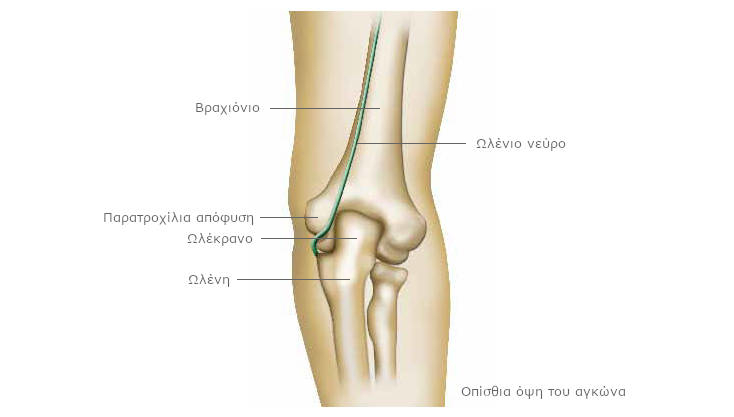

Η άρθρωση του αγκώνα αποτελείται από τρία οστά: το βραχιόνιο, που ενώνει τον ώμο με τον αγκώνα, την ωλένη και την κερκίδα, τα οποία ενώνουν τον αγκώνα με τον καρπό.

Στην εξωτερική πλευρά του αγκώνα βρίσκεται μέρος του βραχιονίου, που ονομάζεται έξω επικόνδυλος. Στο εσωτερικό, δημιουργείται μια σφαιρική επιφάνεια, που σχηματίζεται από το βραχιόνιο, η παρατροχίλια απόφυση (ή έσω επικόνδυλος).

Ανάμεσα σε αυτά τα δυο, μπορείτε να αισθανθείτε το πίσω μέρος της ωλένης, που ονομάζεται ωλέκρανο. Μεταξύ της παρατροχίλιας απόφυσης και του ωλεκράνου σχηματίζεται μια κοιλότητα, που ονομάζεται αύλακα ωλενίου νεύρου.

Το ωλένιο νεύρο διασχίζει το άνω άκρο. Οι διακλαδώσεις του φτάνουν στο μικρό δάκτυλο και τον παράμεσο του χεριού. Είναι μικτό νεύρο: κινητικό και αισθητικό. Διασχίζει την αύλακα που σχηματίζεται ανάμεσα στην παρατροχίλια απόφυση και το ωλέκρανο. Προστατεύεται και συγκρατείται από έναν ισχυρό σύνδεσμο.